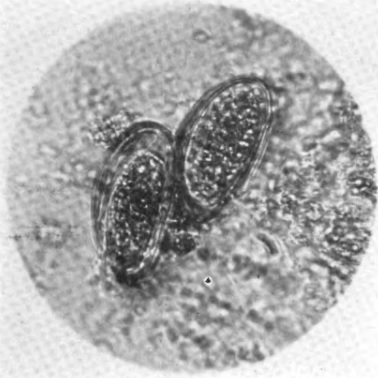

Hookworm, Roundworm, Pinworm, and Other Parasites